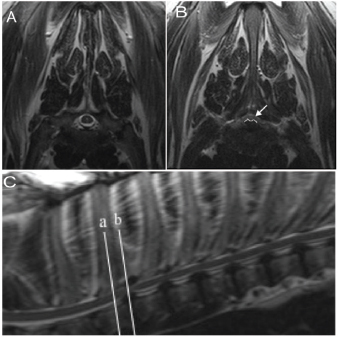

Three dogs and three cats were included in the study, based on clinical signs of neurologic deficits in the hind limbs, consistent with T3-L3 myelopathy (Table 1). MRI (1.5T Symphony, Siemens Healthcare) was used to confirm the diagnosis and site of spinal cord compression. Sagittal and transverse planes of the thoracic spine, including T2-weighted and T1-weighted pre- and post-contrast (Gadoversetamide, Mallinckrodt Incorporated) administration were acquired. Results of MRI were consistent with spinal cord compression in the cranial thoracic spine in all cases (Fig. 1). Two dogs had severe ventral and lateral spinal cord compression from suspected intervertebral disc protrusion while the third dog had moderate lateral spinal cord compression from an extradural meningioma. All cats also had severe spinal cord compression, with MRI identifying a contrast-enhancing mass, diffuse infiltrative process, and spinal canal stenosis.

Fig. 1. (A) Transverse T2-weighted image corresponding to white line a. This is a normal cross section of the spine and spinal cord. (B) Transverse T2-weighted image corresponding to white line b. There is a ventral protrusion of the intervertebral disc, outlined in white, causing moderate spinal cord compression (white arrow). (C) Sagittal T2-weighted image with white reference lines at mid-body T2 and the T2–T3 intervertebral disc space. Multi-level intervertebral disc dehydration and mild ventral protrusion from T3-4 to T7-8 is also evident.